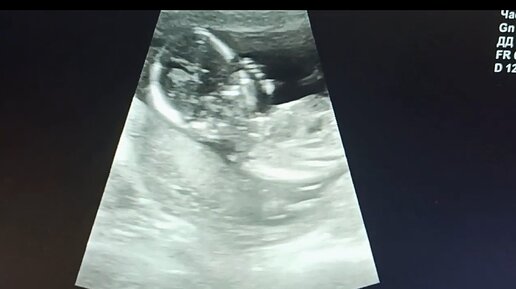

Узи 15 неделя Беременности